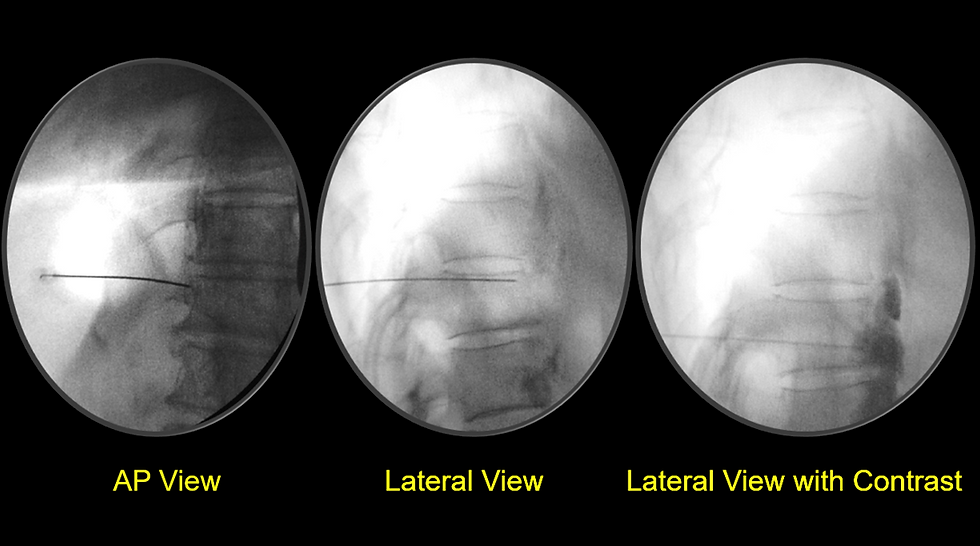

The target area is the anterolateral aspect of the T11 or T12 vertebral body, which corresponds to the path of the greater and lesser splanchnic nerves. The AP fluoroscopic view is used initially to identify the T11–T12 vertebral levels and the lateral edge of the vertebral body.

The needle entry point is located approximately 6–8 cm lateral to the midline, typically at the T11 or T12 transverse process level. Using a 22-gauge, 15 cm spinal needle, the operator directs the needle medially and slightly anteriorly toward the anterolateral corner of the vertebral body.

As the needle approaches the vertebral body, the operator switches to a lateral fluoroscopic view to confirm the depth and avoid overshooting. The needle tip should lie just anterior to the vertebral body but posterior to the aorta or inferior vena cava, depending on the side. It should also remain retrocrural (behind the diaphragm).

After negative aspiration for blood or cerebrospinal fluid, contrast injection is performed to confirm proper spread and avoid intravascular or intrapleural injection.

A small volume of non-ionic contrast agent (usually 2–3 mL of iohexol) is injected through the needle under fluoroscopic guidance.

In the lateral view, contrast should outline the anterior surface of the vertebral body, forming a characteristic teardrop or comma-shaped pattern. This indicates correct retrocrural spread.

In the AP view, the contrast should appear as a bilateral or unilateral crescent adjacent to the vertebral column, without extension into epidural, vascular, or pleural spaces.